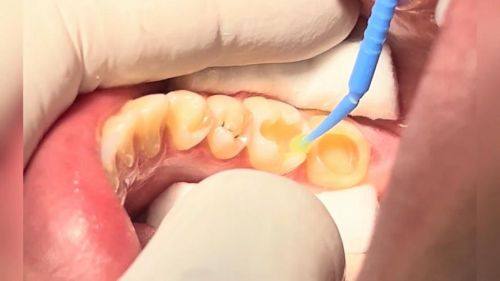

2. 精良设备支持:引进了口腔CT机、数字化口腔扫描仪、赛特丽及EMS超声洁治仪、德国kava喷砂仪、德国meleg真空消毒设备等精良设备,为医生的诊断和治疗提供精细依据,也能减少患者治疗时的痛苦和修复时间。

6. 补虫牙:100元起

3. 我有虫牙,一直拖着没治。来到明嘉齿科后,医生仔细检查后,特别快就给我补好了牙。补牙过程中没有任何不适,补完后牙齿也没有异样感。医生还提醒我要注意口腔卫生,定期检查。这里的医生专精又负责,我特别推荐。